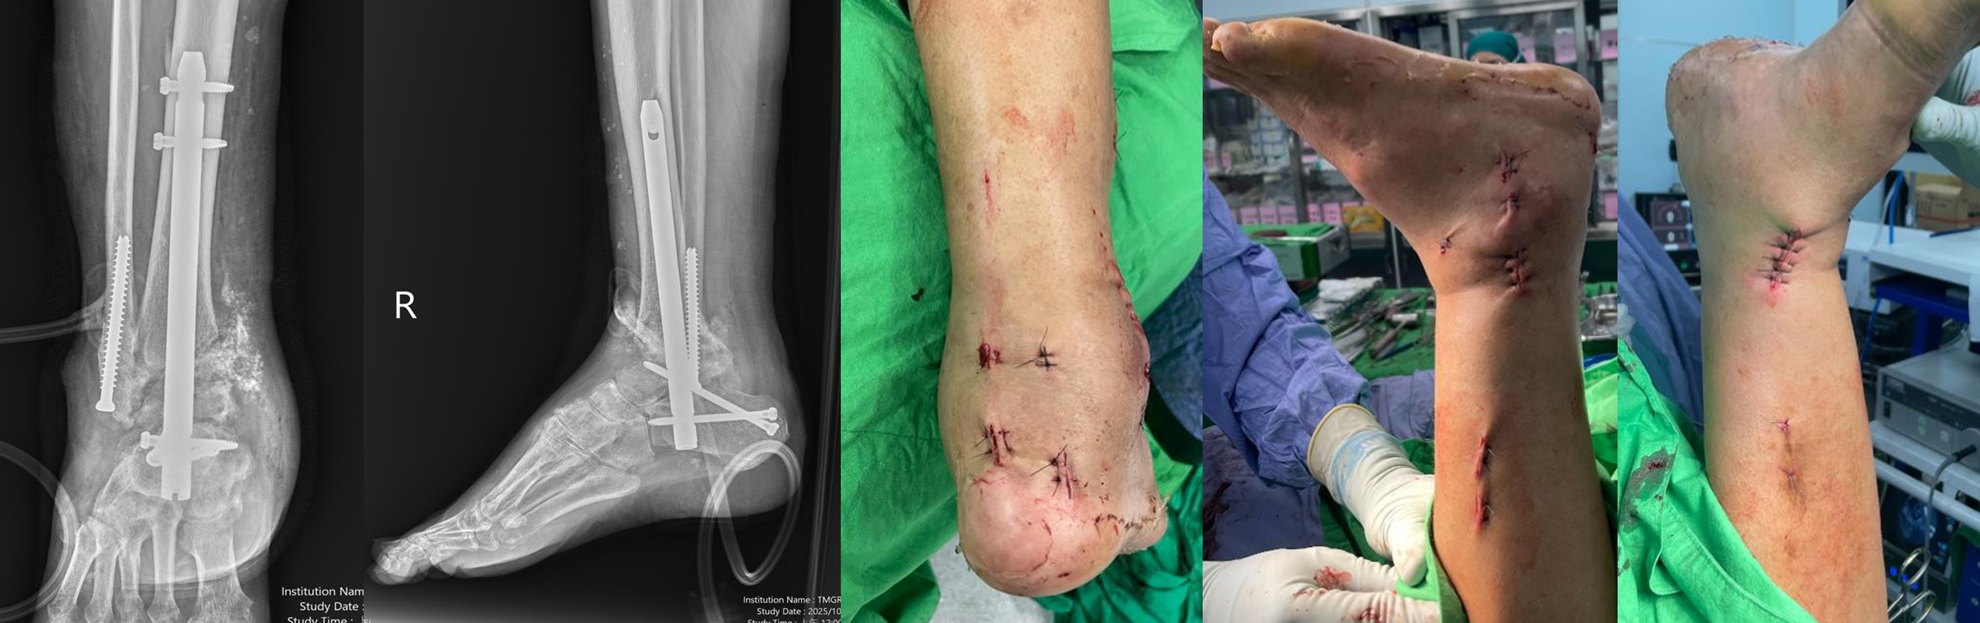

【治療後】鋼釘融合關節

手術完成後,所有傷口皆僅為約 1–2 公分大小的小切口。在骨科專科護理師及病房護理師細心的術後照護下,包括傷口觀察、疼痛評估、血糖控制、下肢循環監測與復健衛教,病人恢復情況良好,疼痛明顯減輕,也大幅降低傷口感染的風險。透過微創關節鏡技術,搭配跨團隊專業合作,即使是重度變形、合併多重內科疾病的踝關節病人,也有機會在安全的前提下接受治療,重新站起來、重拾行走的能力。